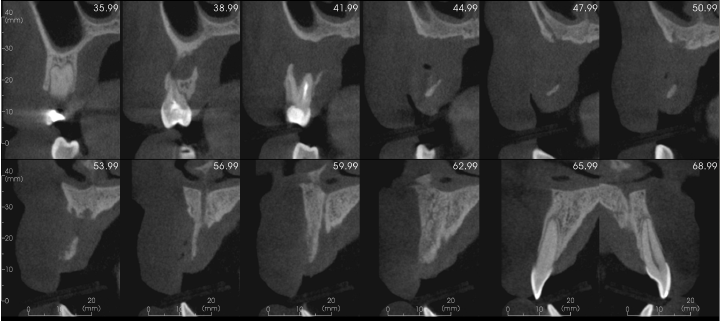

There is a large unilocular moderately well-defined radiolucency, 23 x 15 x 14 mm extending from the UR5 apex to the midline but not invading the nasopalatine canal. There is a “through and through” destruction of the buccal and palatal cortical bony plates, as well as destruction of the alveolar bone ridge. The right maxillary sinus and floor of the nose are not involved. There is external root resorption of the UR4.

The lack of bone expansion, resorption of UR4 roots plus the “floating tooth” appearance of UR4 all suggest the possibility of malignancy. In a case such as this an urgent referral to an oral surgeon is recommended for biopsy to determine the diagnosis and rule out a malignancy.